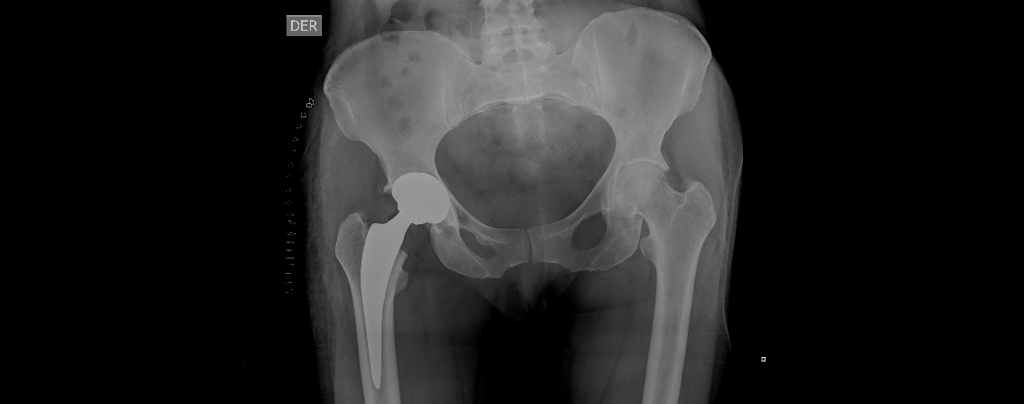

El reemplazo de cadera es una cirugía en la que se retira la articulación de la cadera dañada y se reemplaza por una prótesis artificial (Metal).

Esta intervención es indicada principalmente para pacientes que sufren de artrosis severa o lesiones en la cadera que causan un dolor intenso y limitación en la movilidad.